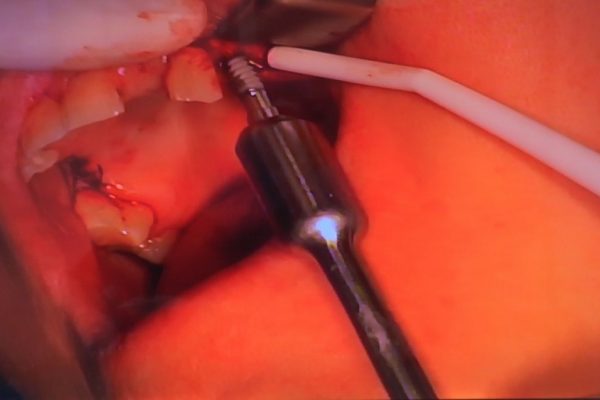

W ostatni weekend czerwca 2018 roku kursanci II Sezonu Preludium Implantologii odbyli piątą, finałową sesję, która w całości podporządkowana była praktyce. W ciągu dwóch dni zabiegowych Lekarze uczestniczący w szkoleniu przeprowadzili szereg zabiegów pod kierunkiem dr n.med. Violetty Szycik. Wszczepili 17 implantów oraz przeprowadzili ekstrakcje i zabiegi regeneracyjne kości. Zabiegi były wykonywane także w sedacji dożylnej z udziałem specjalisty anestezjologii i intensywnej terapii dr Jolanty Grzybowskiej. Preludium implantologii to nowy program edukacyjny dla adeptów implantologii stomatologicznej, którego celem jest wprowadzenie do implantologii poprzez pozyskanie wiedzy w szerokim zakresie i uwzględnieniem szczegółów mających decydujące znaczenie dla powodzenia leczenia implantologicznego. Ale tak jak wszystkie szkolenia w Instytucie Vivadental, w tym wiodące Practiculum Implantologii, zorientowane jest na praktyce i samodzielnym wykonywaniu zabiegów pod kierunkiem Mentora. To najlepsza edukacja w medycynie zabiegowej, a zarazem najlepszy start do implantologii.